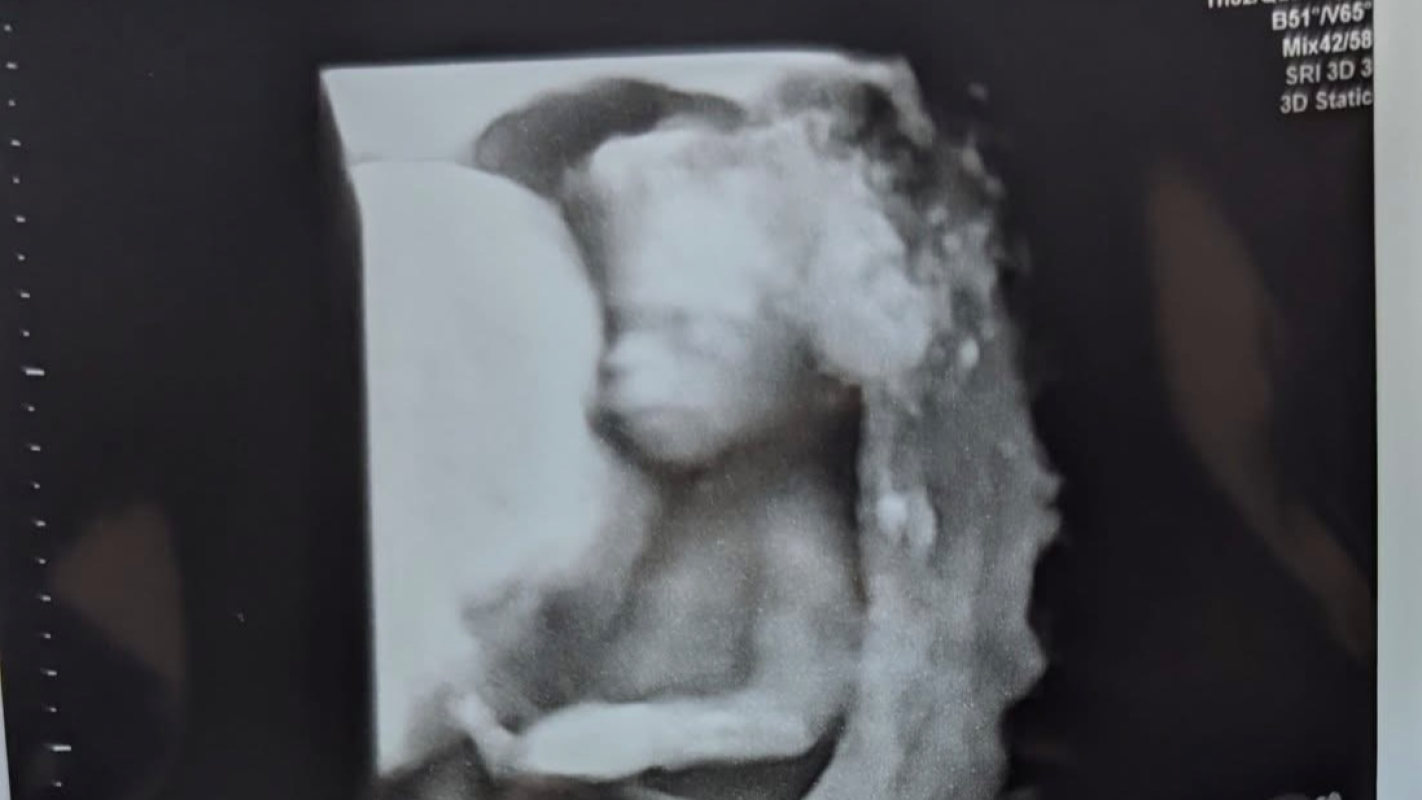

It is with heavy hearts that we reach out to you today to support Matt and Laci during an unimaginable time. On Wednesday, March 5th, they went to their anatomy scan to check on their precious baby boy, Kohen Henry Clark, only to learn there was no heartbeat. The following day, they had another appointment to confirm the heartbreaking news—Kohen’s heart had stopped, and his growth had ceased. The couple has undergone testing to better understand what may have caused this devastating loss.